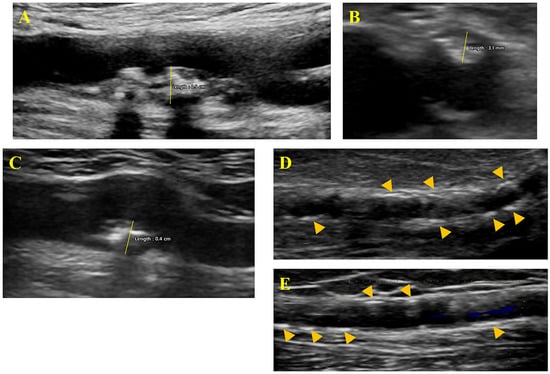

All ultrasound visual material was stored and examined offline in the core ultrasound laboratory by an experienced imaging technician who was not blinded to patient group allocation. For each measurement, the operator conducted three repeated acquisitions and recorded the value considered most accurate, typically reflecting an internal average. Repeated measurements generally showed a variation of less than 10%. IMT was assessed at the distal far wall of both the right and left common femoral and carotid arteries, and the average value was documented. PT was measured in the axial or longitudinal view in the femoral territory and only in the longitudinal view in the carotid territory (Figure 1). The maximal PT observed on either side (for both carotid and femoral arteries) was recorded. The radial artery was scanned for any signs of calcification, but only clearly defined hyperechoic areas with acoustical shadowing were considered positive findings (Figure 1).

Figure 1. Vascular ultrasound assessment—measurement of femoral plaque thickness in longitudinal (A) and axial (B) view; measurement of carotid plaque thickness in longitudinal view (C); identification of distinct radial artery calcifications—arrow heads (D,E).